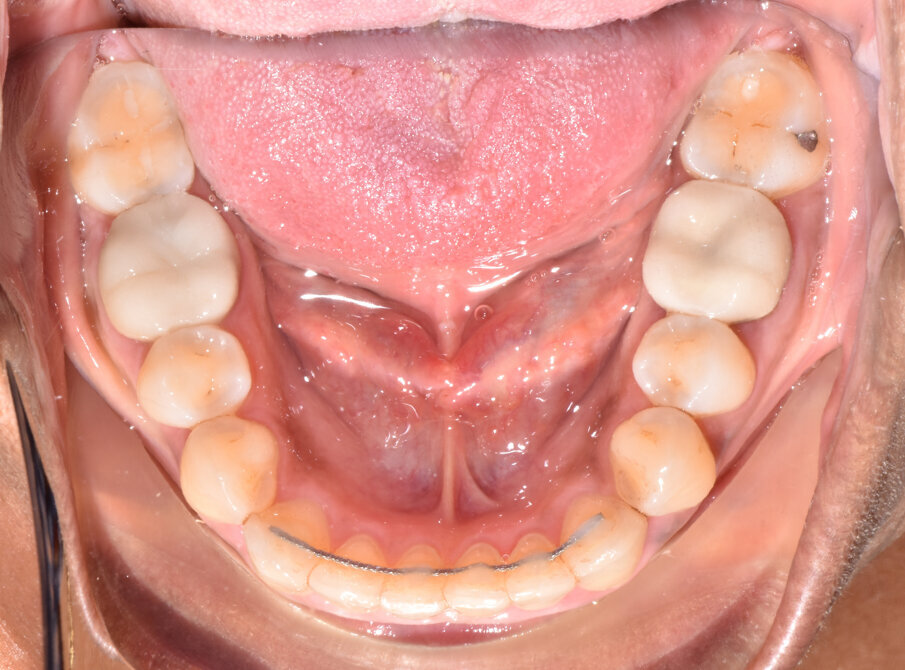

A 56-year-old female patient presented with a Class III malocclusion, anterior crowding and a 2-3 mm anterior open bite. Clinical photographs showed an ideal incisor display upon smiling. The panoramic film was unremarkable, and the lateral cephalometric film revealed a negative 1 mm overjet. (Figs. 1 to 10)

Lower arch expansion and interproximal reduction of 0.5 mm were prescribed on all of the lower incisors from mesial of canine to mesial of canine before the 19th aligner. (Fig. 13) IPR would allow retraction to assist the Class III elastic correction of the negative overjet. Additionally, since counterclockwise autorotation of the mandible would project the lower incisors anteriorly, retraction would also assist in mitigating this effect.

Retraction and uprighting of the lower incisors would also achieve relative extrusion, further assisting in the closure of the anterior open bite. (Figs. 14,15)